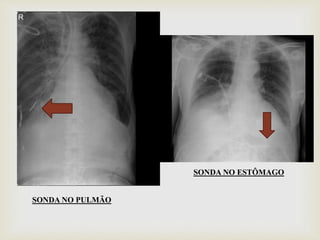

 Após passagem da SNE, deve ser feito um raio x e

mostrar ao médico, para certificar que a sonda esta

locada adequadamente, só assim a dieta pode ser

liberada.

SONDA NO PULMÃO

SONDA NO ESTÔMAGO